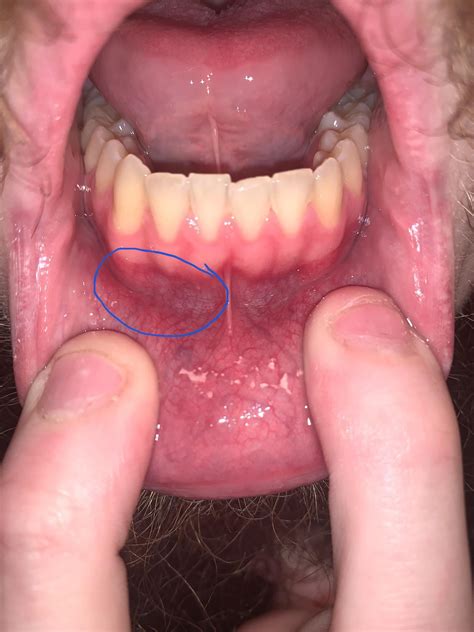

Possible small white bump? I’m not quite sure what it is. : r/askdentists